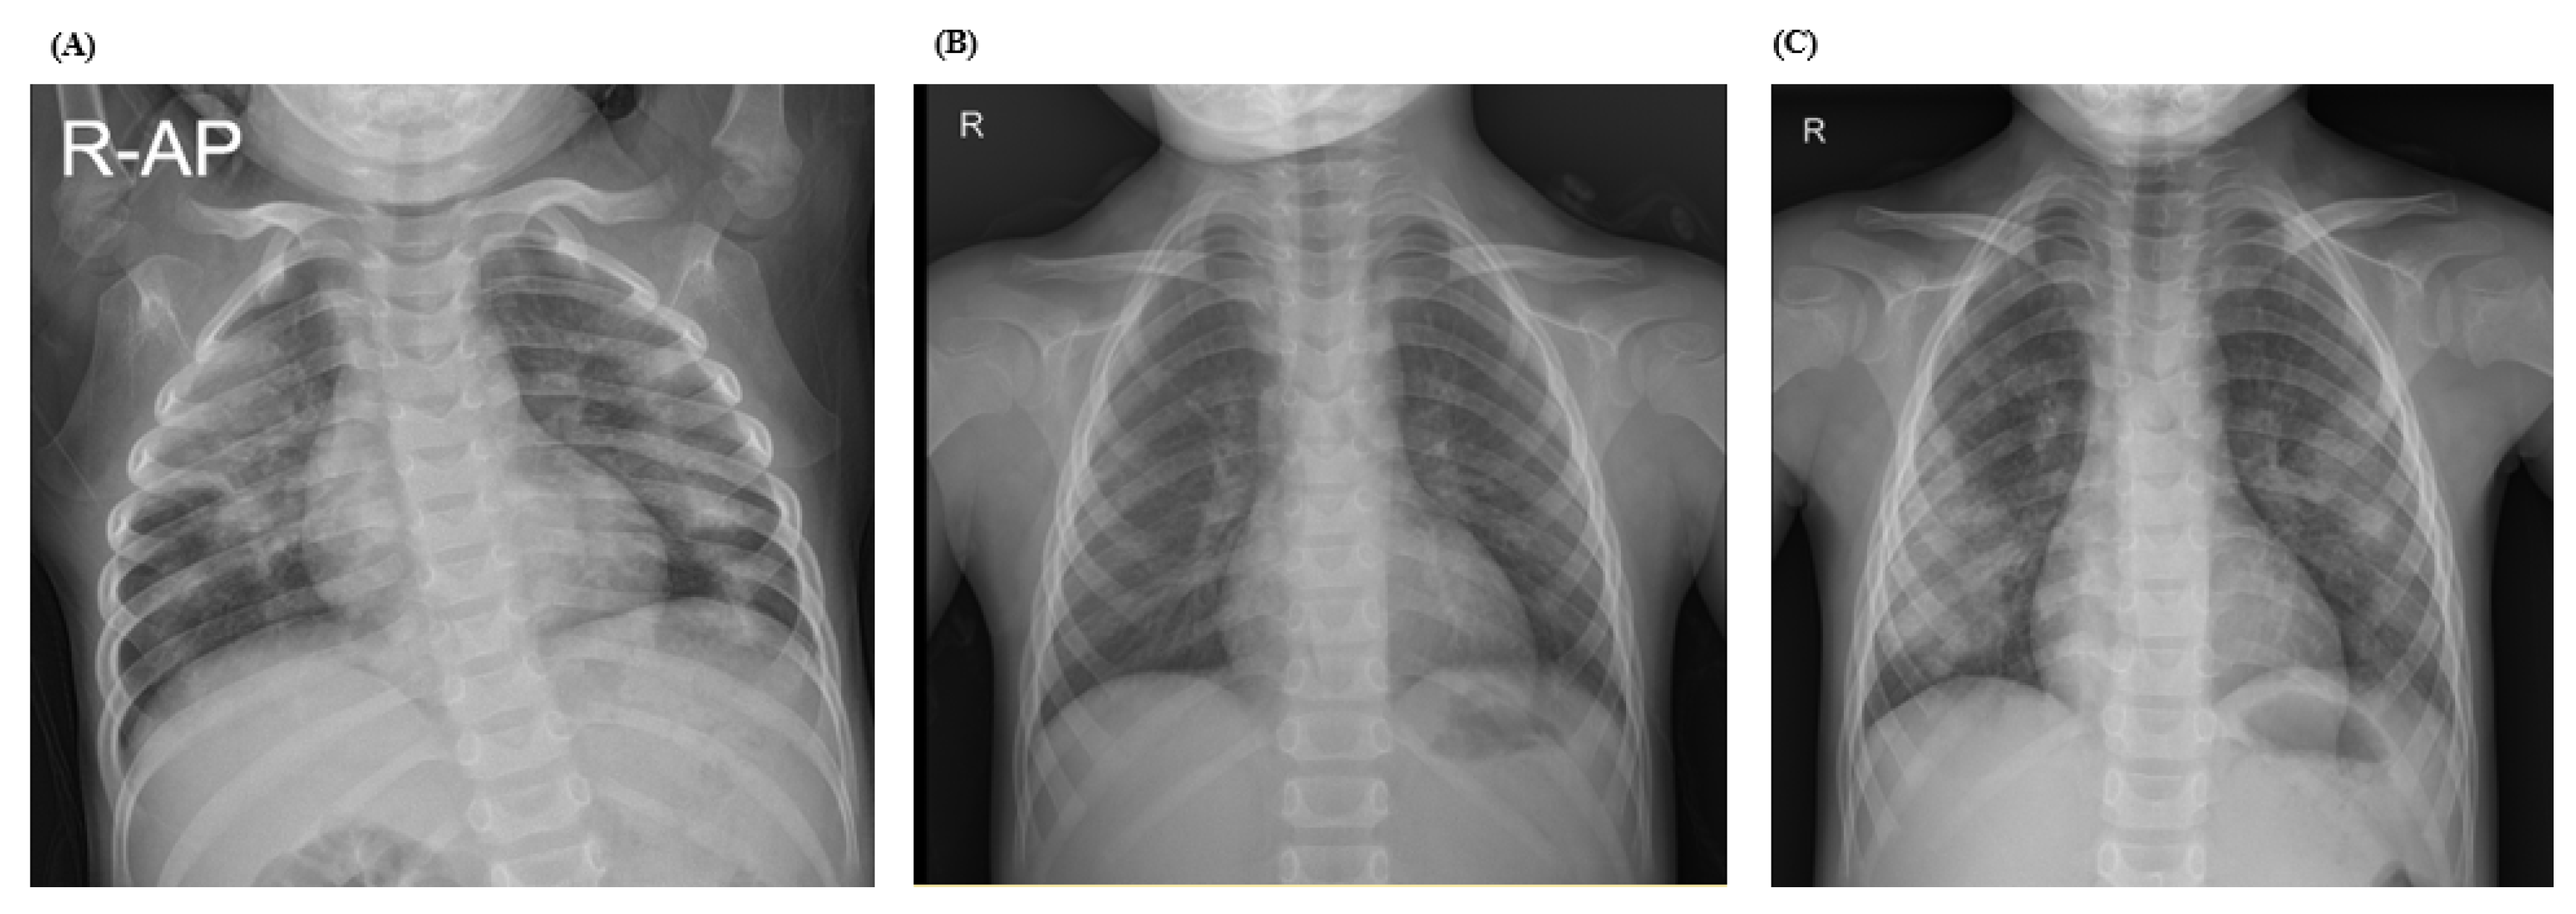

| Chest radiograph | Multifocal patchy consolidation | ||